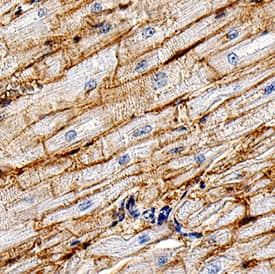

CD36/SR-B3 was detected in immersion fixed U937 human histiocytic lymphoma cell line using Rabbit Anti-Human CD36/SR-B3 Monoclonal Antibody (Catalog # MAB19554) at 8 µg/mL for 3 hours at room temperature. Cells were stained using the NorthernLights™ 557-conjugated Anti-Rabbit IgG Secondary Antibody (red; Catalog # NL004) and counterstained with DAPI (blue). Specific staining was localized to cytoplasm. View our protocol for Fluorescent ICC Staining of Cells on Coverslips.CD36/SR‑B3 in Human Heart.

CD36/SR-B3 was detected in immersion fixed paraffin-embedded sections of human heart using Rabbit Anti-Human CD36/SR-B3 Monoclonal Antibody (Catalog # MAB19554) at 3 µg/mL for 1 hour at room temperature followed by incubation with the Anti-Rabbit IgG VisUCyte™ HRP Polymer Antibody (Catalog # VC003). Tissue was stained using DAB (brown) and counterstained with hematoxylin (blue). Specific staining was localized to cardiomyocyte membranes. View our protocol for IHC Staining with VisUCyte HRP Polymer Detection Reagents.Applications for Human CD36/SR-B3 Antibody

Immunohistochemistry

Sample: Immersion fixed paraffin-embedded sections of human heart